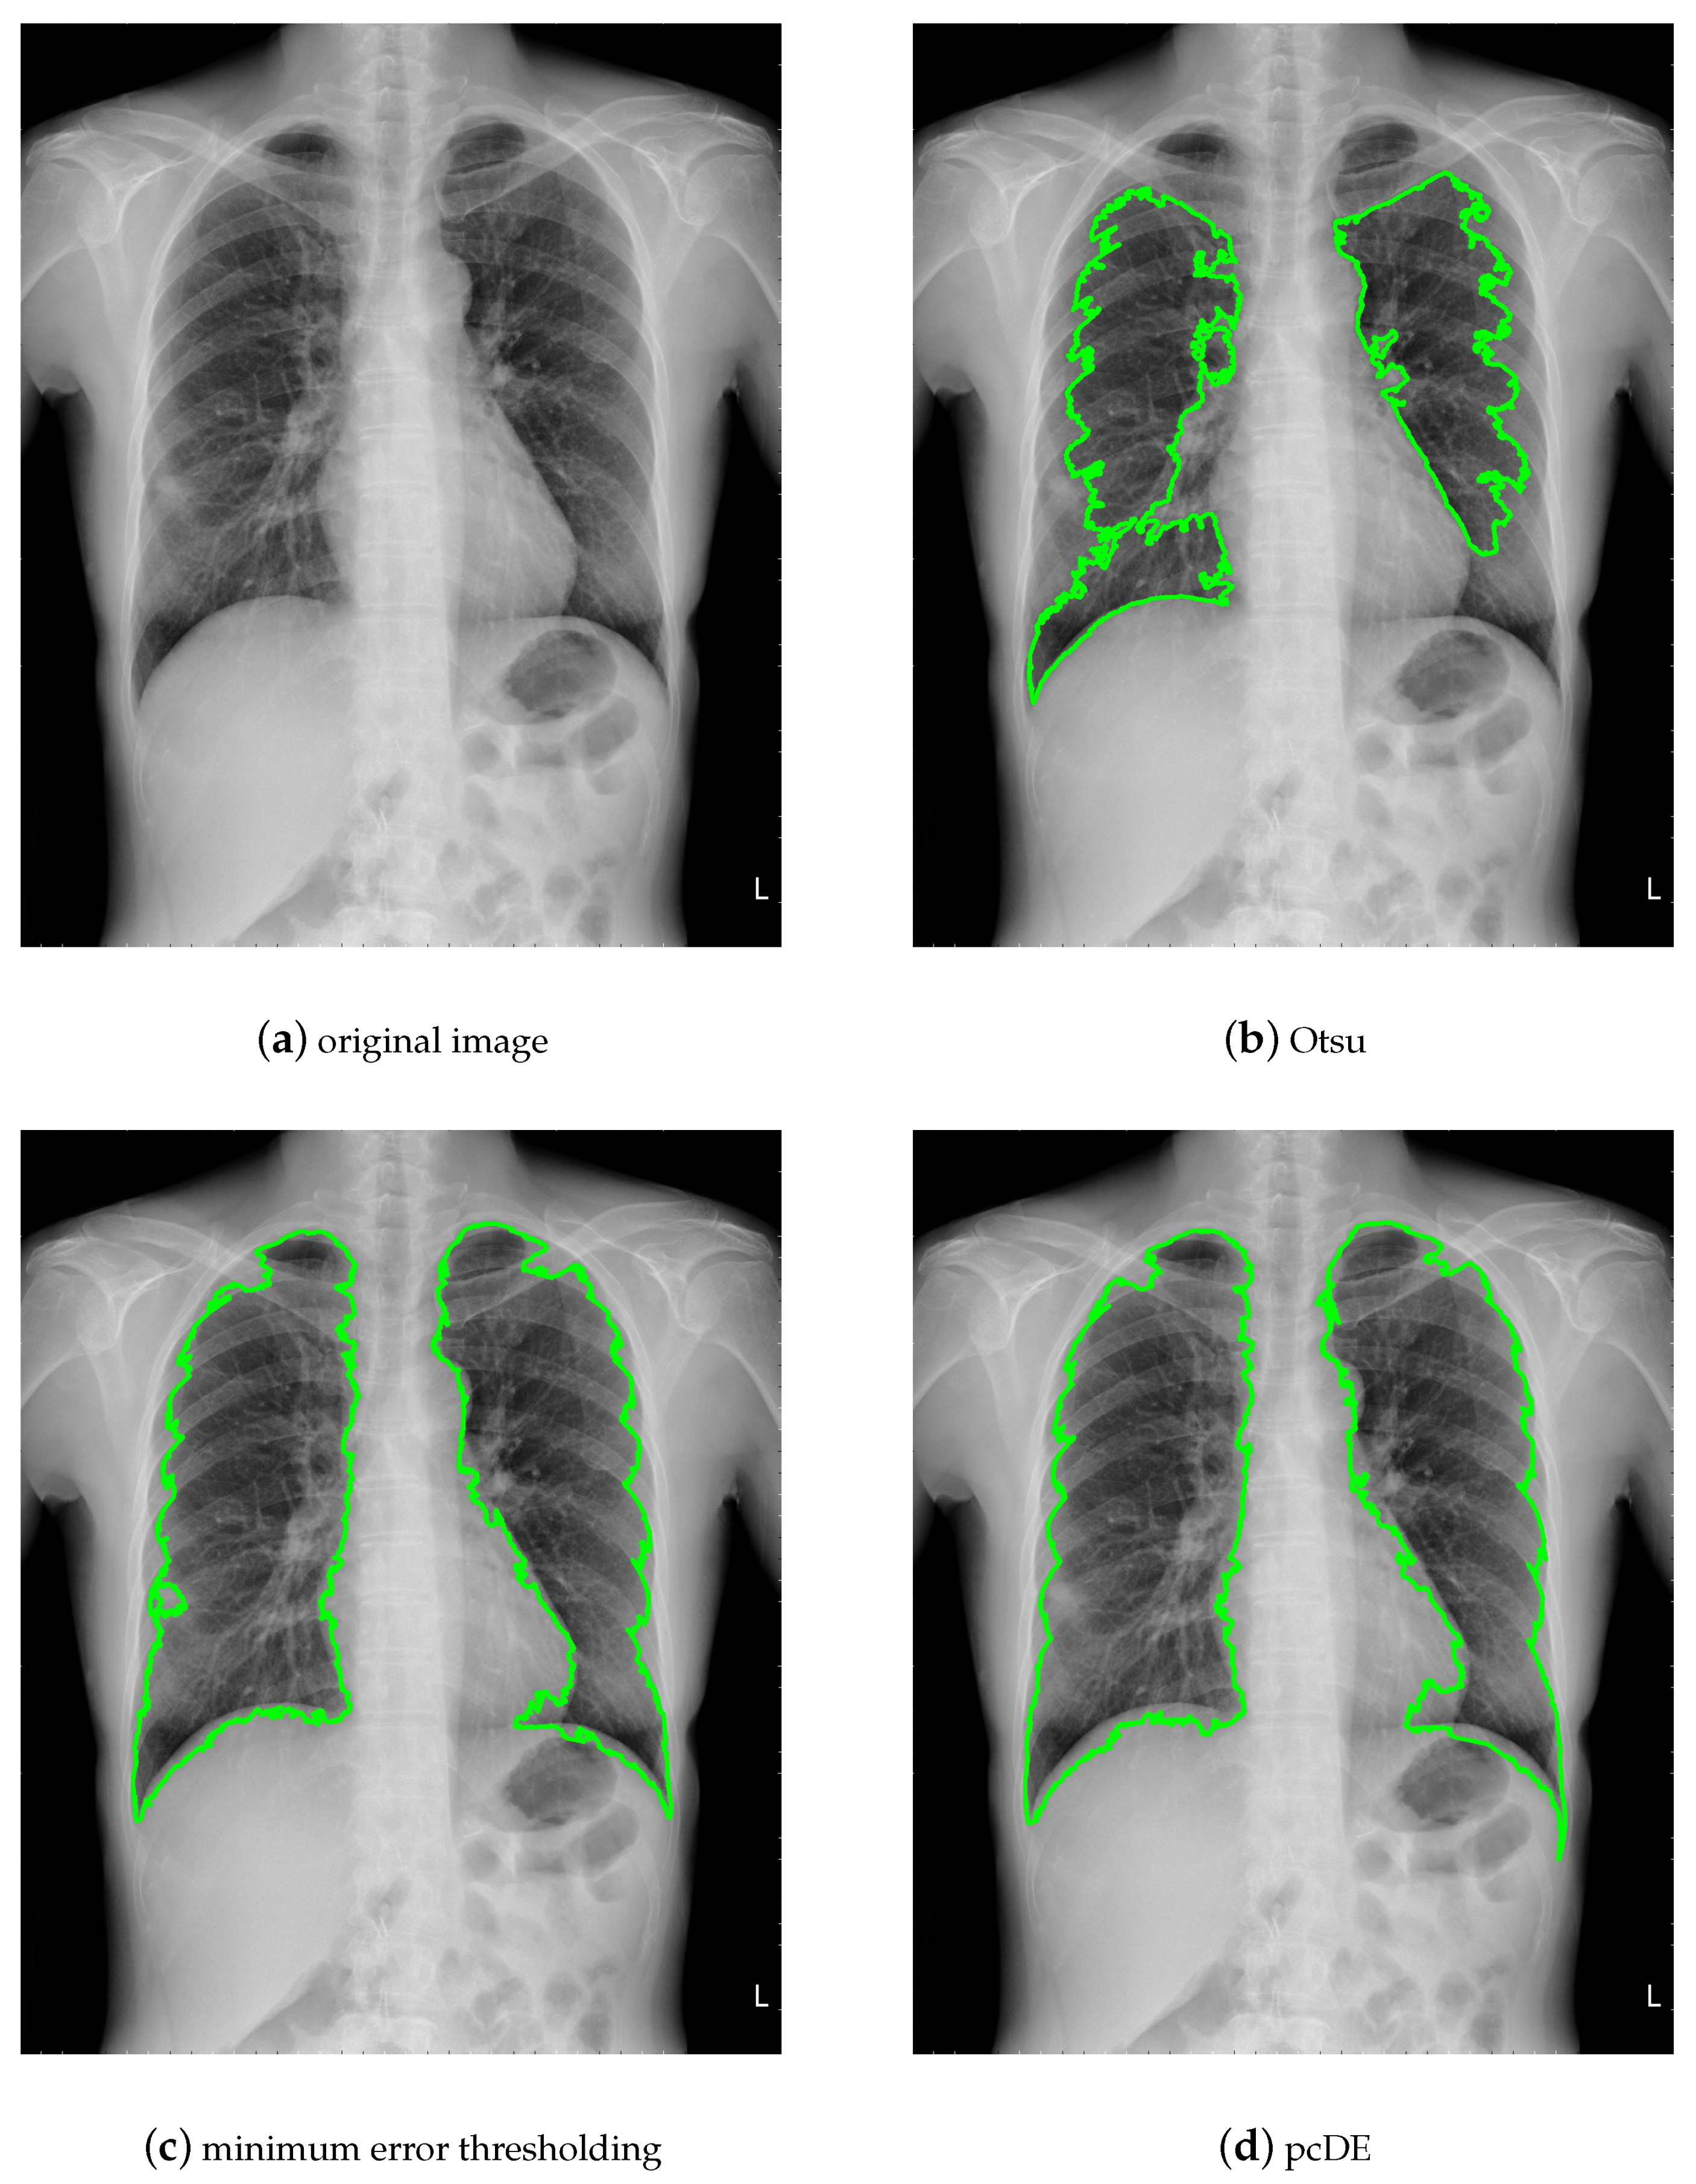

5. Case of Study: Parallel Compact Differential Evolution for Image Segmentation

- Image preprocessing. Enhance the contrast of the image to achieve better segmentation.

- Calculate the optimal threshold for image segmentation through different methods to get the binarized image.

- Use morphological methods to process images to extract targets.

- Mark target contour.

- : Represent the result of ground truth segmentation (Figure 13).

- : Represent the result of algorithm segmentation.

| Segmentation Method | Original Image | Noisy Image |

|---|---|---|

| Otsu | 0.9210 | 0.9531 |

| minimum error thresholding | 0.9732 | 0.9093 |

| pcDE | 0.9738 | 0.9684 |